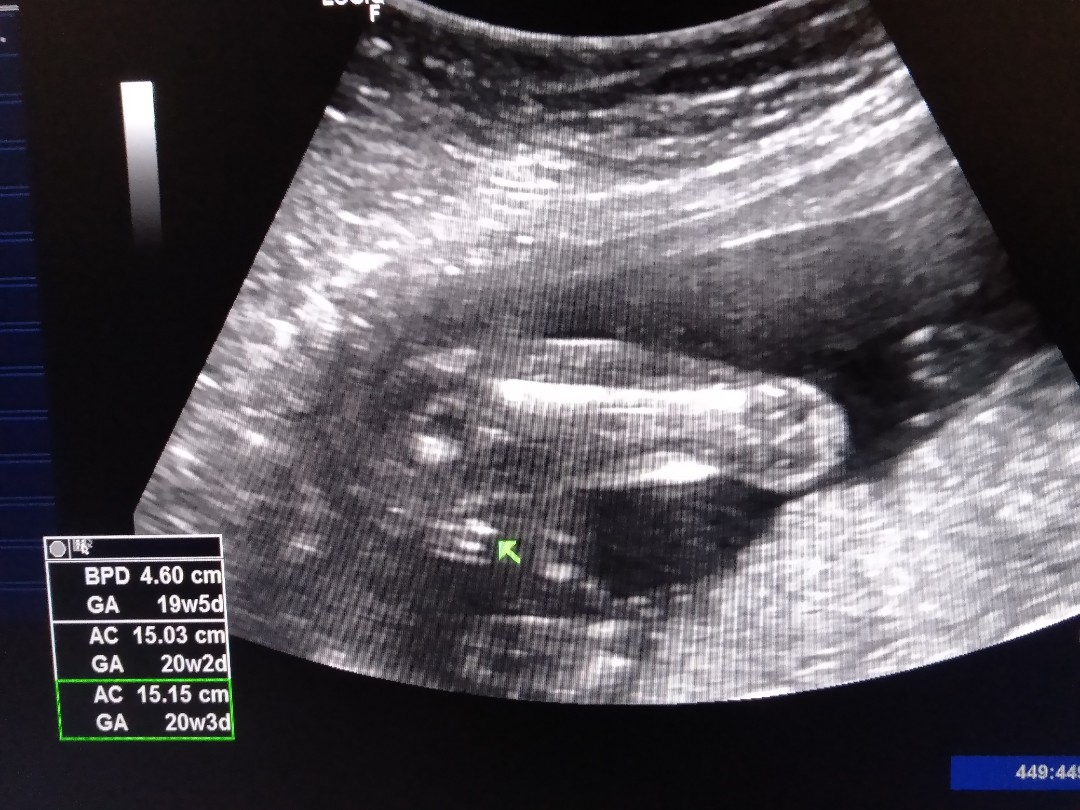

เห็นเพศตอน19วีคลูกสาวจ้า

20wค่ะหมอบอกลูกสาว